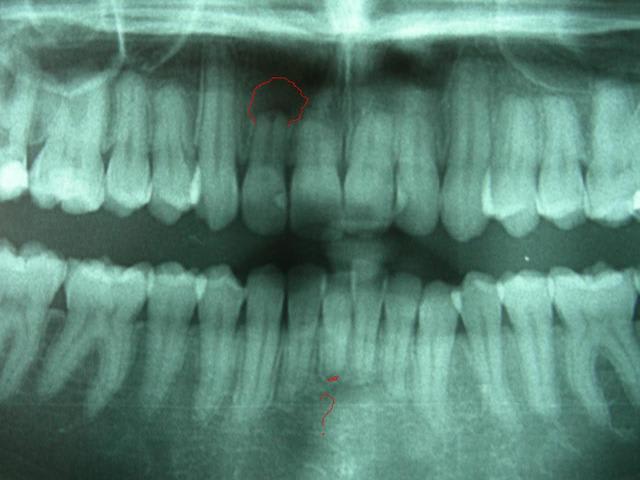

Radios2 xkcqei - Eugenol

Radios3 oiwhej - Eugenol

Bonjour Val, est ce bien des rhizalyses qu'on apercoit sur les incisives supérieures??

rhizalyses aux incisives sup et inf,14-24-25 touchees aussi,cela fait beaucoup et freine pour reprendre sereinement un traitement MB

rotations a corriger(encore un risque de rhizalyse)

plus un angle interincisif ferme

Pour la 12, ce qui vous inquiète est sa coloration. J’ai lu 3 ou 4 articles ou il était montré que les rhizalyses Sup. se stabilisaient souvent.

Par contre, et par expérience personnelle, les inférieures sont plus fragiles.

Et il me semble soupçonner un début de commencement, d’introduction au préliminaire d’un préambule de granulome inférieur.

pour la 41 , image à verifier, mais pour la 12, je ne serais pas inquiet que de la coloration. Mais à verifier aussi. Il faut se méfier des pano.

- il s'agit bien évidemment de rhizalyses dont la cause iatrogène orthodontique est plus que fortement suspectée : d'abord avec la plaque palatine dont je suppose qu'elle avait un rôle pour favoriser l'éruption de 23 (par désinclusion ? je l'ignore)dont le manque de place et l'éruption haute ont laissé une dénudation radiculaire importante ainsi que l'occlusion non fonctionnelle venant ajouter la sanction finale.

De plus il s'agit (s'agissait) d'une CL II.2 dont lors du TT Mb , la demande en torque incisif de par la pression labio-jugale est intense et accroit le risque de rhizalyse.

- on objective au moins 6 incisives rhizalysées soit un peu moins de 1/4 de la denture

- contexte CL II,2, hypodivergent, hypertonicité musculaire labio-jugale.

- nécessité d'ingression et d'hypertorque incisif qui est un facteur aggravant dans les rhizalyses.